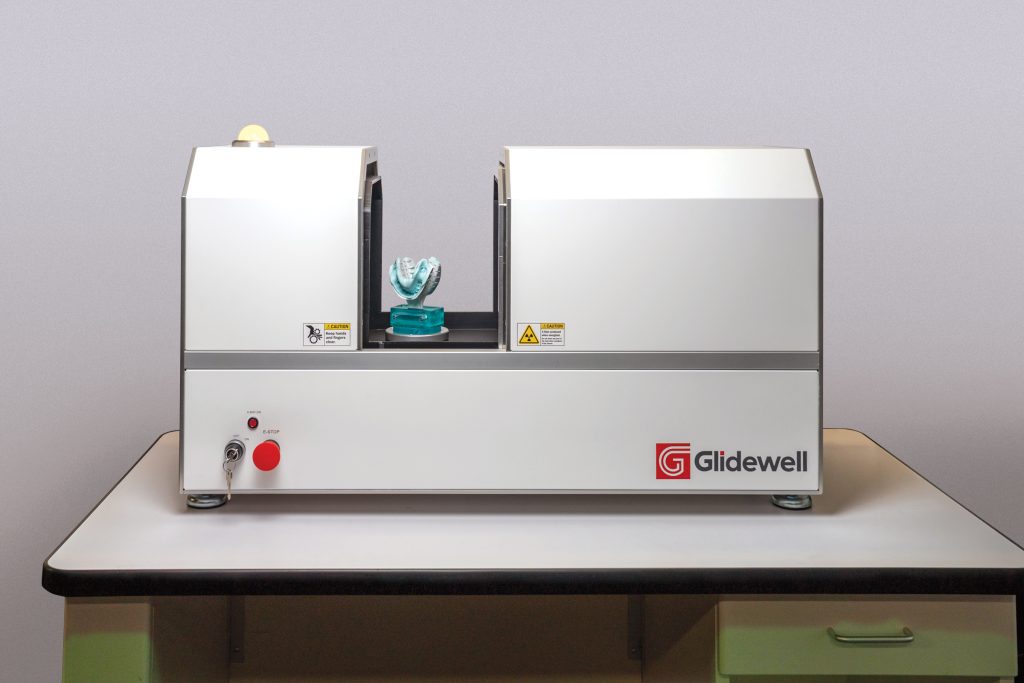

Introducing Our New 3D CT Scanner | Chatham Dental Centre

dentistinsteveston.com

dentistinsteveston.com

ct 3d scanner dental introducing our cone beam

How A Dental Lab Is Shaking Up CT Scanning - FacFox News

facfox.com

facfox.com